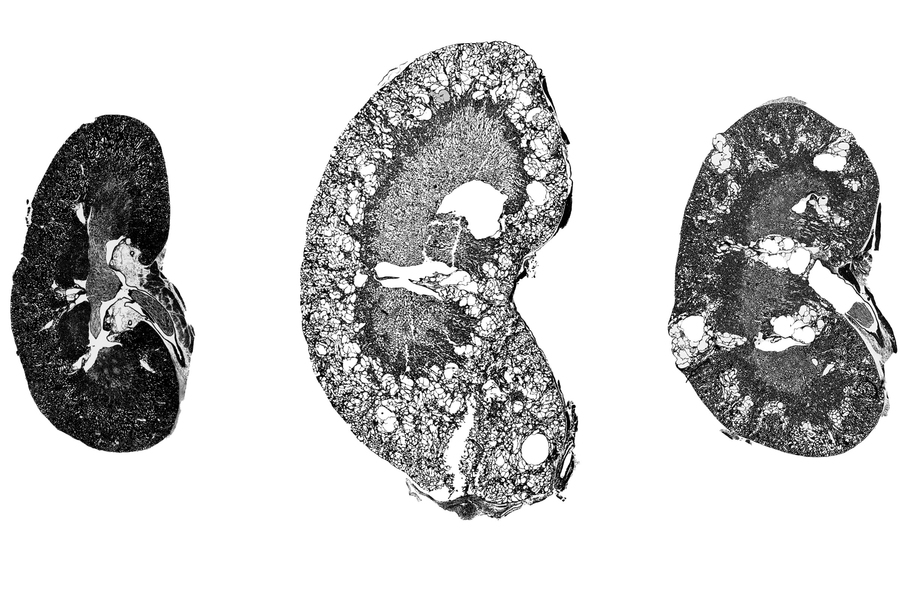

Медицинские изображения и объяснения агенезии почки

Раздел: Снимки-откровения